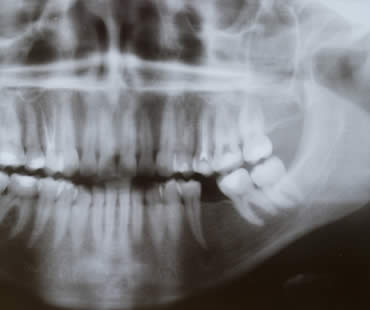

Wisdom teeth got their name because they are the final teeth to develop, usually in the late teens to early twenties, at a time when a person becomes fully mature or “wise.” Wisdom teeth are the third and final set of molars in the very back of the mouth. Most people...